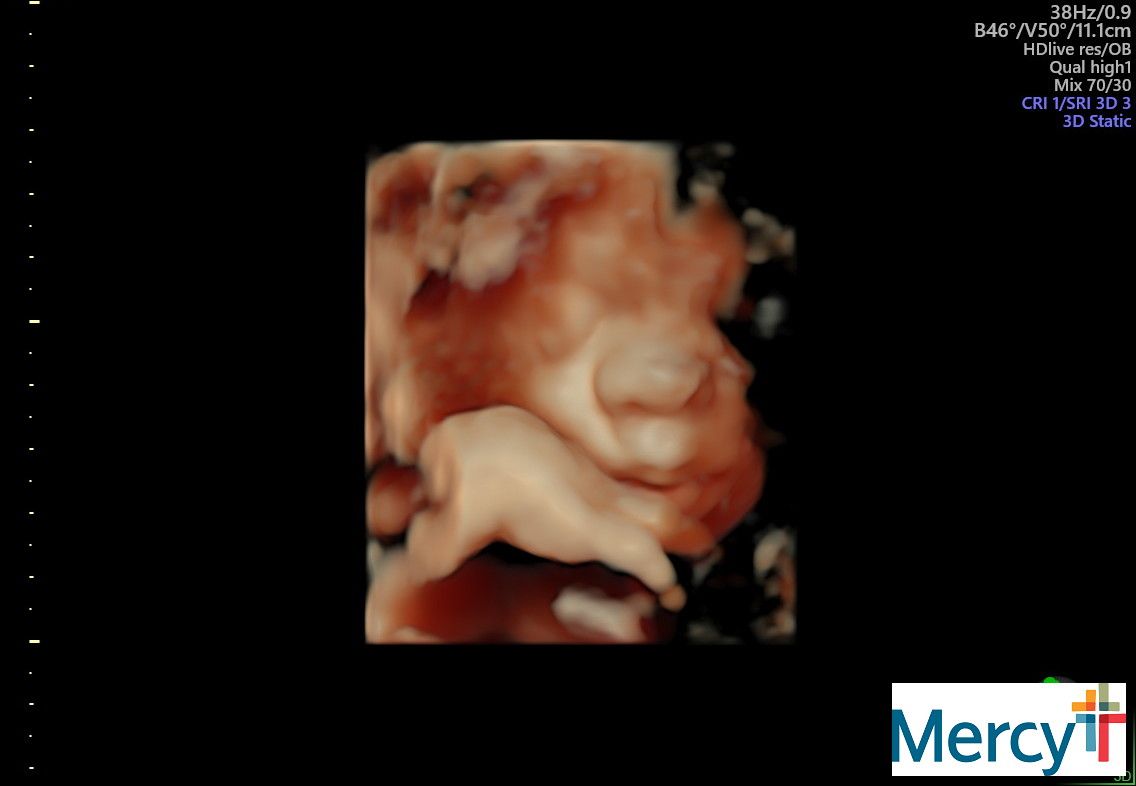

The belly is in full swing! Look at this face!